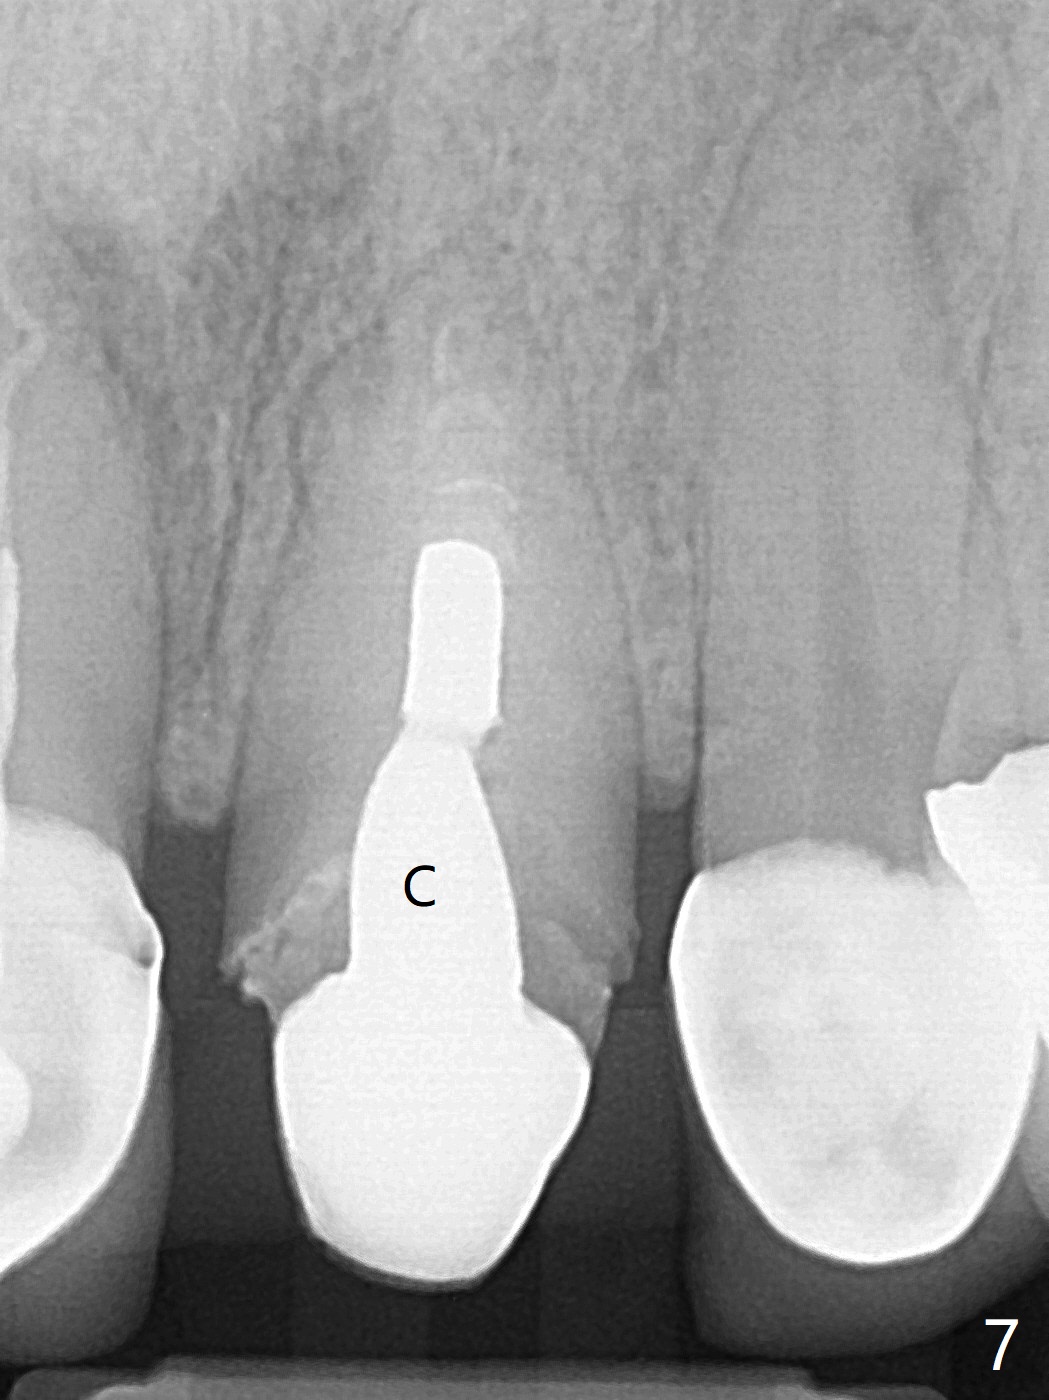

A 51-year-old woman with poor dentition has history repeated dislodged crown and post at #9. Finally the post fracture (Fig.1). After discussion of treatment options, she chooses to save the tooth. Treatment plan is to remove post, possible RCT retreatment, redo post and crown. The post remains stable following lengthy use of Piezo scaler (Fig.2). It appears that Piezo is quite aggressive, removing the tooth structure and the metal. Finally the coronal portion of the post is removed for cast post (Fig.3). There is approximately 2 mm for ferrule effect (Fig.4). The cast post is cemented with RelyX Ultimate and prepared for crown (Fig.5-7).